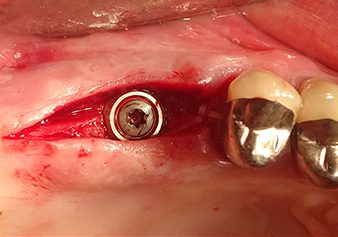

Situation after insertion of the implant

Рис.9: Ситуация после установки имплантата (длина: 10 мм, ортопедическая площадка: 6,5 мм) непосредственно перед наложением швов